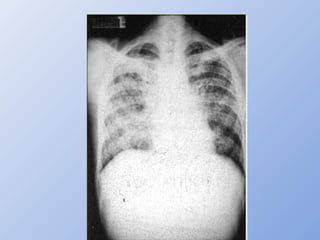

– Rx: nódulos isolados ou múltiplos nos campos pulmonares

médio e inferior

V - ManifestaçõesClínicas • Pulmonar – Imunocompetentes - infiltrados pulmonares que se resolvem espontaneamente, resultando em granulomas cicatrizados – Imunocomprometidos • Infecção primária ou reativação de focos pré-existentes • Disseminação • Estabelecimento de infecção no SNC – Tosse, febre, perda de peso, dispnéia – Rx: nódulos isolados ou múltiplos nos campos pulmonares médio e inferior